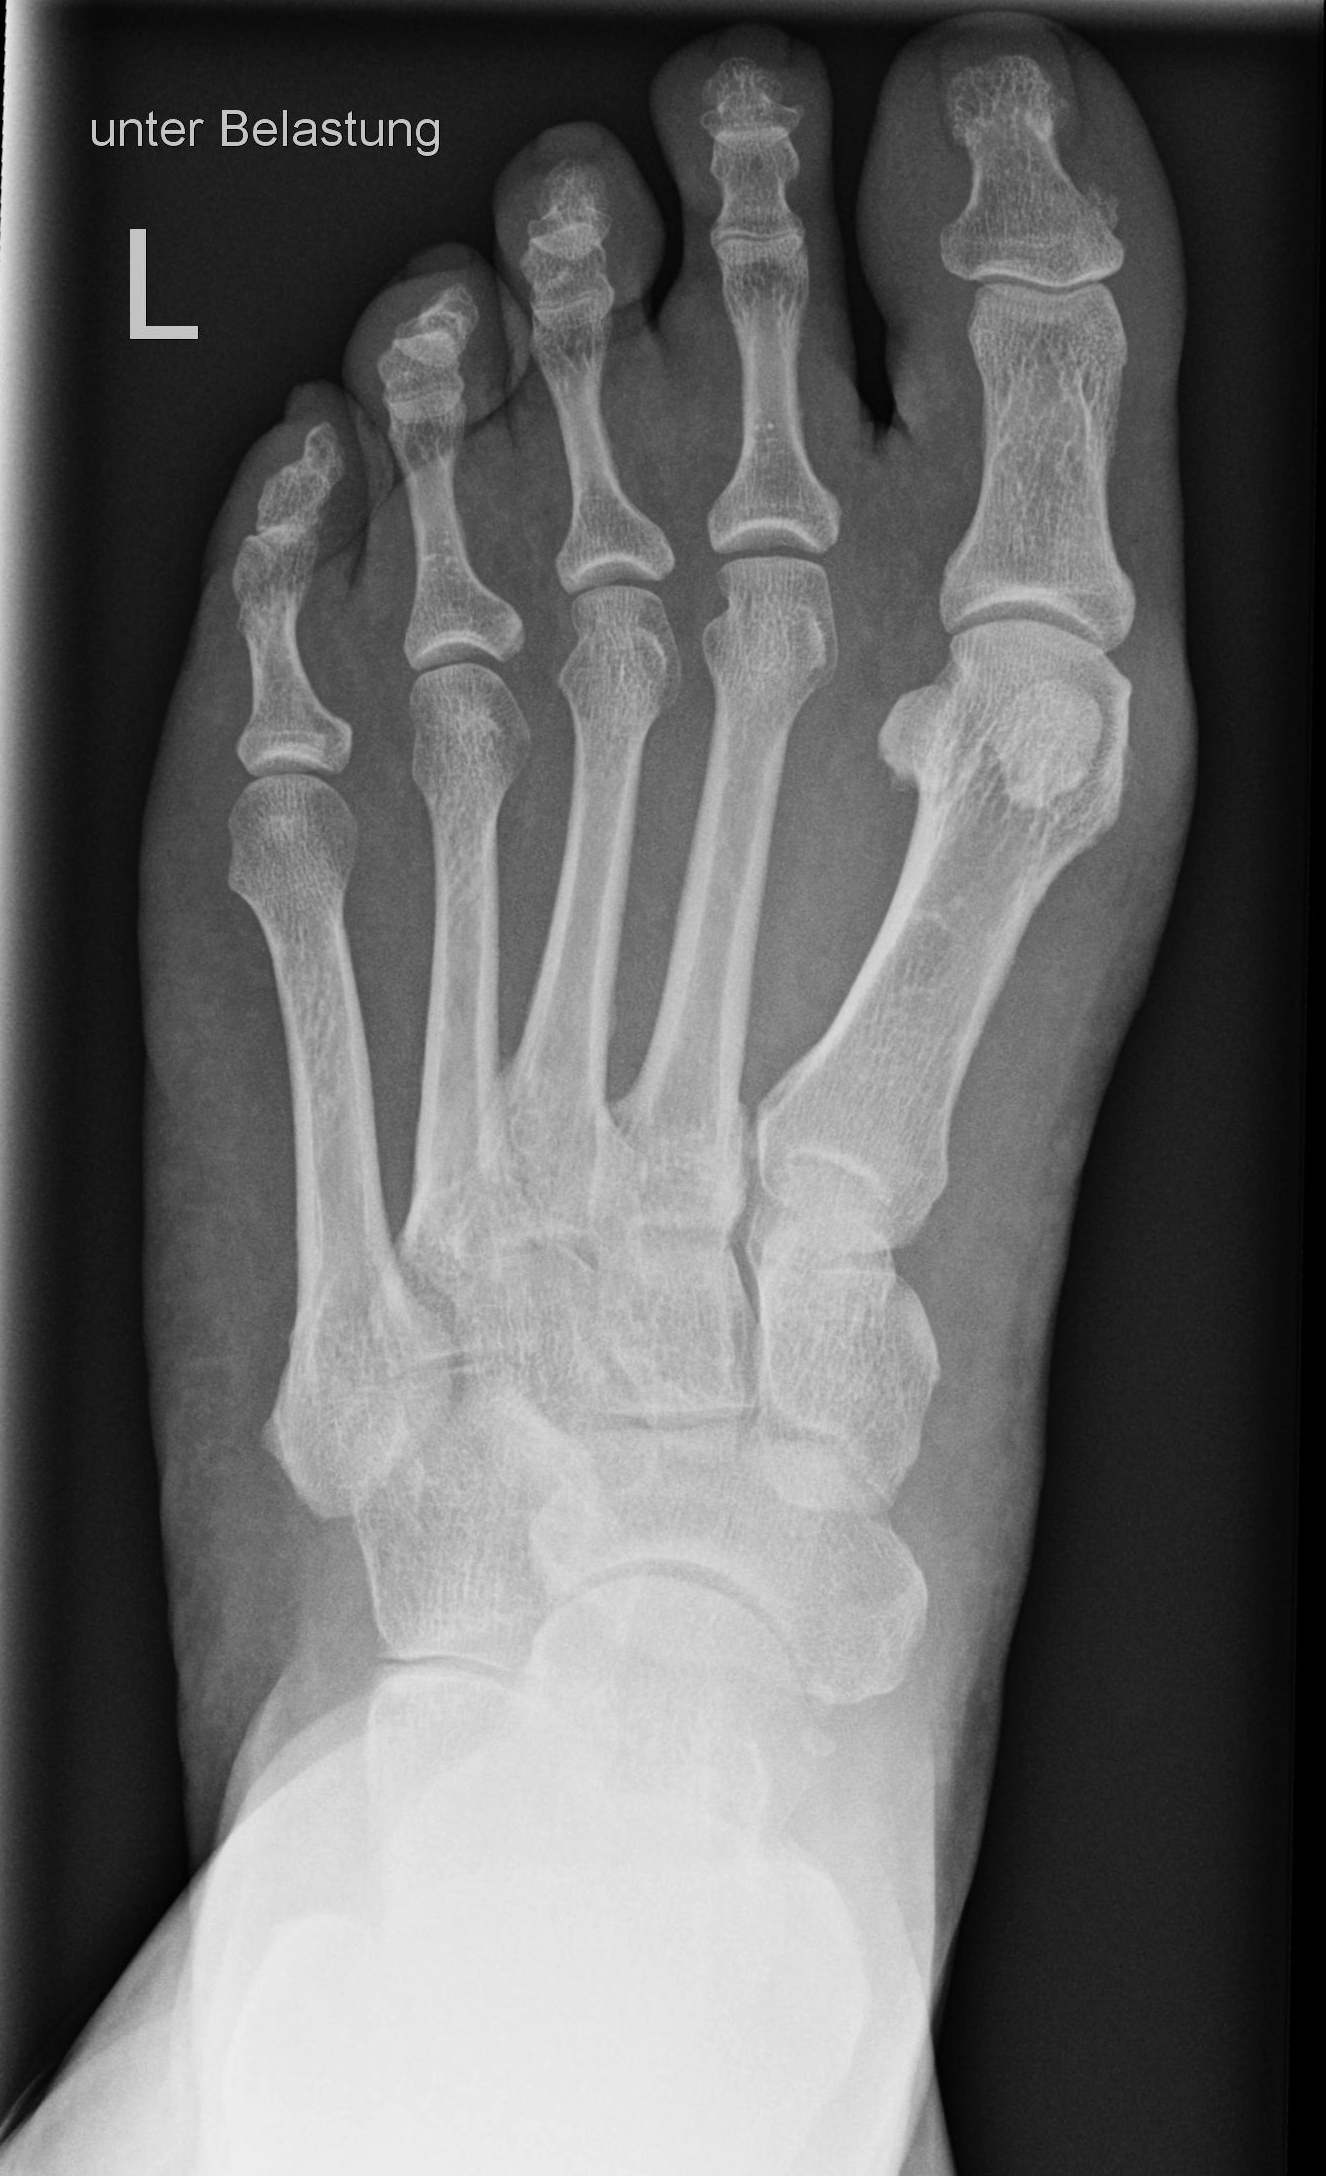

Fuß dorso-plantar (a.-p.) unter Belastung

stehend auf Bildempfänger

Knie leicht gebeugt und zweiten Fuß nach hinten versetzen um das Gleichgewicht zu halten

Es soll eine Belastung auf den Fuß erfolgen, aber nicht so, dass das Knie und die Bleischürze genau über dem Fuß schweben.

Leicht Kippung zum Patienten auf Objektmitte

Häufig passiert es, dass der Patient mit seinem Knie zu sehr über den Fußrücken kommt bzw. ins Lichtvisier. Deshalb mit dem zweiten Fuß einen leichten Schritt nach hinten machen und kontrollieren, dass das Knie und die Bleischürze nicht über dem Fuß schwebt.

Vollständige überlagerungsfreie Darstellung des ganzen Fußes a.p.